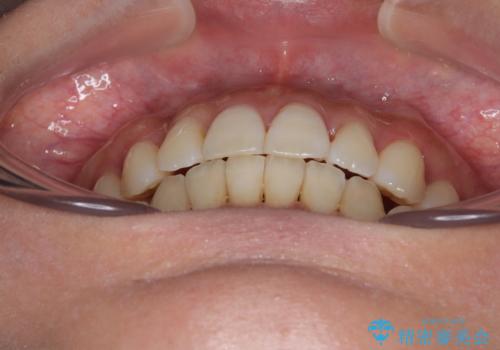

【モニター】上顎前突と奥歯の鋏状咬合 補助装置を用いたインビザライン矯正治療

- 前歯の歯列不正と奥歯の咬みにくさを気にして来院された患者様です。

インビザラインでの矯正治療を希望されていましたが、奥歯の咬み合わせがインビザライン単独では改善困難と判断されたので、補助装置を併用することとしました。

上顎最後臼歯は極端に外側を向いており、下顎骨に対して上顎骨が前方に位置していたため、補助装置により最後臼歯を一気に内側に引き込むとともに、上顎臼歯を後方移動させ、奥歯の咬み合わせが改善した後に、上下インビザラインにより歯列全体を整えていくこととしました。

奥歯の咬み合わせを事前に望ましい位置に改善したことで、インビザライン単独では改善が最も困難な状況を排除することができ、非常に理想的な仕上がりとなりました。